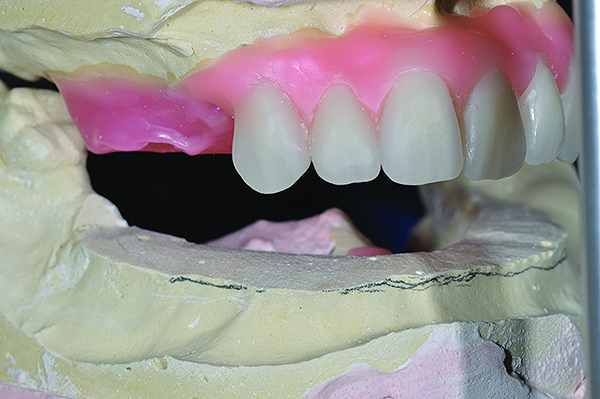

Completed diagnostic wax-up for maxillary and mandibular All-on-4 full-arch rehabilitation.

Figure 6